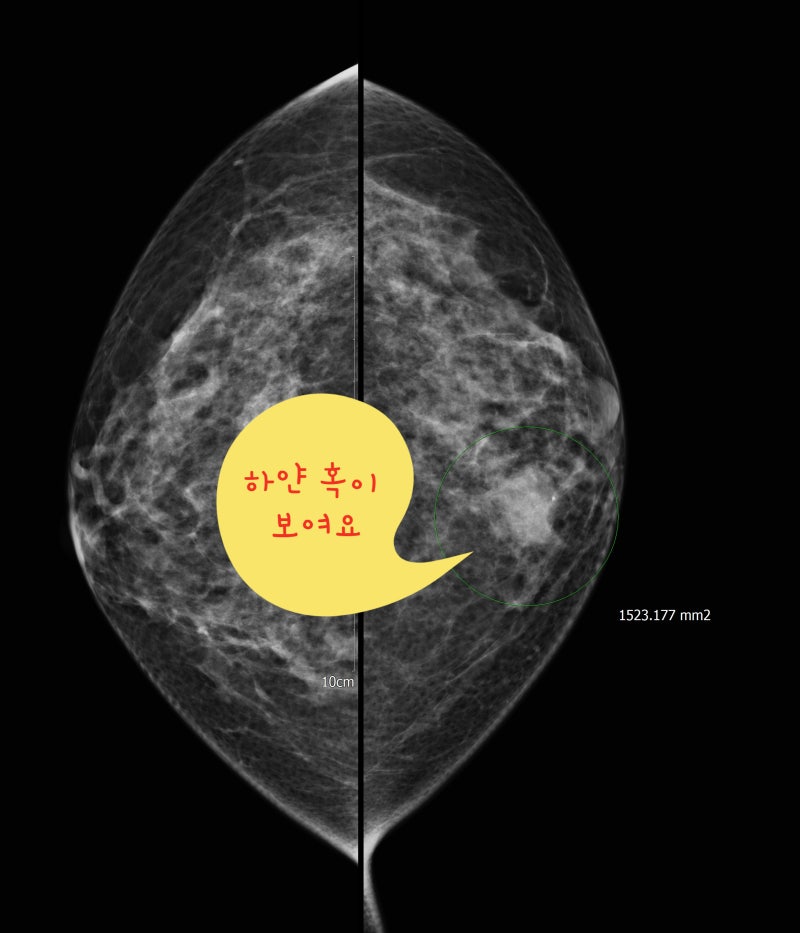

초기 유방암, 즉 1기 이하의 유방암은(겨드랑이 전이 없이 2cm 이하의 유방암) 만져지기 어려운 경우가 많습니다. 매년 유방 촬영과 유방 초음파 검사를 하지 않으면 초기에 유방암을 진단할 수 없습니다.유방 촬영술은 미세 석회화를 진단하는 데 좋은 검사 방법입니다. 미세 석회화만의 경우는 0기 유방암 또는 1기 유방암 소견입니다.유방 초음파 검사는 유방의 응어리를 진단하는 데 좋은 검사 방법입니다. 1기 이상 유방암은 대부분 유방 초음파 검사에서 응어리로 진단됩니다.

유방 촬영에서 미세 석회화 소견은 유방암일 가능성이 있습니다.

유방촬영술로 군집한 미세석회화 소견을 볼 수 있습니다. 0기 유방암 소견입니다.초기 유방암 사진유방 초음파 검사상 1cm 유방몽울입니다. 1기 유방암 진단을 받았습니다. 3 초기 유방암이 의심되는 응어리가 있을 때 조직검사유방에 혹이 진단되어 유방암인지 양성종양인지 정확한 진단이 필요한 경우 먼저 침총조직검사를 실시하십시오.젖클리닉위드심의원유방에 혹이 진단되어 유방암인지 양성종양인지 정확한 진단이 필요한 경우 먼저 침총조직검사를 실시하십시오.젖클리닉위드심의원유방침 총조직검사 동영상 접속 —> https://blog.naver.com/breastkim/221808987454유방몽울 총조직검사 <총생검> 과정 : 위드심 유방클리닉 김미혜 원장(전) 김미혜유 클리닉 원장 유방에 응어리가 진단되어 유방암인지 양성종양인지 정확한 진단이 필요하다면 먼저 침총조직검사를 해야함… blog.naver.com유방의 바늘 총 조직 검사 1. 유방 진료상 유방에 종괴이 진단되었습니다. 암입니까?유방 암의 대부분은 암이 아닌 양성 종양입니다.그러나 씨앗 덩어리 모양이 나쁘거나 크기가 커질 경우는 암을 의심하고 조직 검사를 해야 합니다. 2. 바늘 총 조직 검사는?<바늘 총 조직 검사>는 바늘을 유방 종괴에 넣어 일부 조직을 채취하는 조직 검사입니다.5개 이상의 조직을 채취해야 정확한 진단이 가능합니다.상처는 1mm정도로 거의 남지 않습니다.<바늘 총 조직 검사>는 전 세계적으로 널리 이루어지고 있는 유방 암 확진 방법으로 정확도는 99~100%입니다.3. 검사 방법 1) 누운 자세로 실시합니다.2)초음파 검사를 하면서 종륜 부위와 피부를 조금 부분 마취합니다3)바늘을 넣고 씨 덩어리에서 조직을 채취합니다. 조직을 채취할 때마다 “빵”소리가 납니다만, 통증은 없습니다. 5개 이상의 조직을 채취해야 하므로 5번 정도”빵”소리를 낼 있습니다.4)검사가 끝난 뒤 반창고나 붕대로 가슴을 닫습니다.4. 검사 시간 검사 시간은 5-10분에서 결과는 7일 이내에 전화로 알립니다.침총 조직 검사에서 꺼낸 유방 응어리 조직입니다.위 조직을 특수염색하여 현미경으로 조사하면 정확한 조직검사 결과가 나옵니다.섬유선종 특수염색 후 현미경 사진–>유방암 특수염색 후 현미경 사진 5. 검사 결과가 유방암으로 진단되면 대학병원으로 빠른 시일 내에 연결해 드리겠습니다.양성종양 진단 시 안심하셔도 되지만 *종양 크기가 큰 경우 *모양이 좋지 않은 경우 *사이즈가 커지는 종양*고위험 병변의 경우 <맘모톰 수술>을 권장합니다.유방암 진단을 받은 경우 빠른 시일 내에 대학병원으로 연계하여 치료받을 수 있도록 도와드리겠습니다.https://blog.naver.com/simjsmc/222505127069추악한 유방암에 대한 조직검사: 맘모톰 수술? 침총조직검사? : 분당위드심유방클리닉 못생긴 유방암에 대한 조직검사 : 맘모톰수술을 할까요? 침총 조직검사를 할까요? 안녕하세요 46살입니다… blog.naver.com4 초기 유방암이 의심되는 미세 석회화가 있을 때 유방조직검사미세 석회화가 모여 있을 때 <군집된 미세 석회화>라고 합니다. 이 소견의 20~30%가 0기 유방암일 수 있지만 나머지 70~80%는 양성으로 진단된다고 합니다.이를 정확하게 진단하기 위해 미세 석회화를 조직 검사하는 방법은 두 가지가 있습니다.첫 번째는 바늘 총조직 검사입니다.미세석회화 소견이 유방 초음파 검사에서 보이는 경우 <침총조직검사> 방법이 가장 좋습니다. 부분 마취 아래에 볼펜 정도의 바늘을 넣고 조직을 채취하면 되기 때문입니다.유방암의 미세 석회화 사진–>유방촬영술에서 흰 반점과 같은 미세석회화 소견이 모여 있는 군집화 미소석회화 소견입니다.유방초음파검사에서 작은 혹과 미세석회화 소견이 보입니다 침총조직검사로 조직을 채취하고 있습니다유방암으로 진단되어 <대학병원 유방센터>로 연결하였습니다.읽기용 슬라이드, 사진 등 치료에 필요한 자료를 모두 준비하여 예약해 두었습니다.두 번째는 맘모톰 수술입니다.유방석회화맘모톰수술병원위드심의원미세석회화소견이유방초음파검사에서볼수있는경우<침총조직검사>방법이가장좋습니다. 그러나 유방 초음파 검사에서 보이지 않는 경우는 맘모톰 수술을 해야 합니다.먼저 유방 촬영으로 석회화 부분에 바늘을 넣습니다.유방 촬영술로 바늘이 잘 들어가 있습니다.바늘이 들어있는 부분에서 맘모톰 수술로 석회화를 뽑아냅니다.->꺼낸 조직을 다시 유방 촬영술을 해서 석회화 소견이 나왔는지 확인하겠습니다.이 사진을 검체 촬영술 specimen mammography라고 합니다.이 사진에서 흰색 석회화 소견이 나왔는지 확인해야 합니다.0기 암 진단을 받았습니다.대학병원 유방센터로 연결해드렸습니다. 초기 유방암은 생명에 지장 없이 완치되는 아주 작은 유방암입니다.주로 0기 1기 유방암을 초기 유방암이라고 부릅니다.증상이 없는 경우가 많기 때문에 정기적으로 유방 초음파 검사를 해주셔야 진단할 수 있습니다. 검사상 이상 응어리나 미세석회화 소견이 있는 경우 <침총조직검사>를 시행하는 것이 가장 좋으며 <맘모톰수술>이 필요할 수 있습니다.분당위드심의원 김미혜원장 프로필바로가기—>분당위드심의원 김미혜원장 프로필바로가기—>